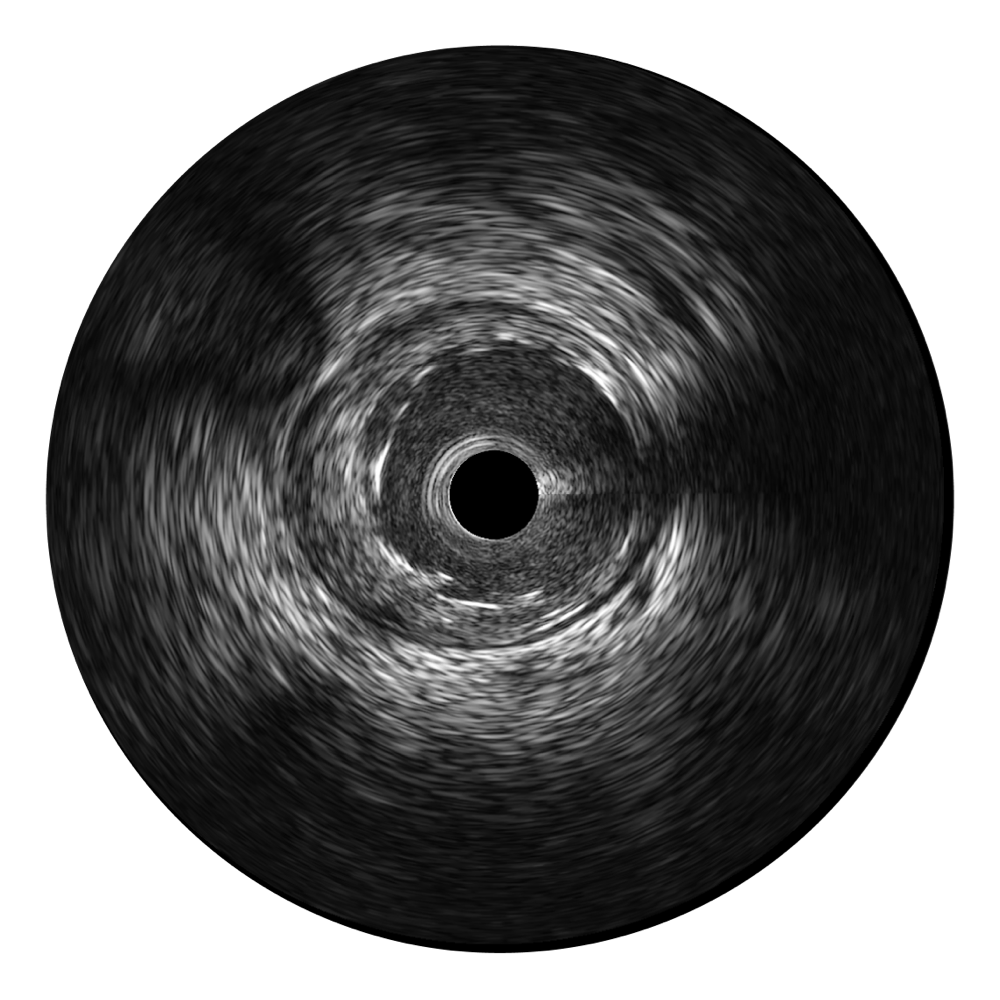

玖鼎集团宽频IVUS图像

对比传统IVUS导管成像,玖鼎集团宽频IVUS图像的近场支架梁显影更细腻,远场中膜外血管仍清晰可辨,兼顾远中近,兼顾分辨力与穿透深度